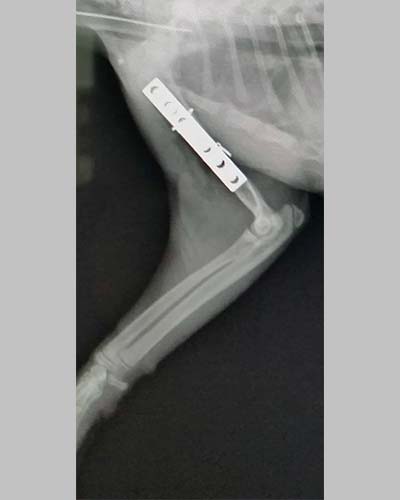

外力撞擊造成肱骨骨折的喵咪 手術完整的復位

回診時患肢已可負重,在診間呼嚕呼嚕的樣子跟一開始痛到抓狂判若兩貓